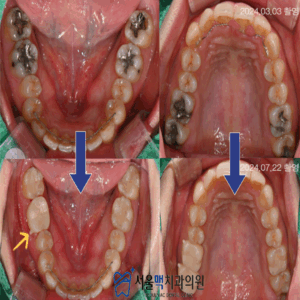

26. 가양역치과 전체 임플란트와 함께 수직고경 상승을

가양역치과 전체 임플란트와 함께 수직고경 상승을 🗒️목차🗒️ – 무너진 교합 회복 – 세심한 진단부터 살펴봐야 – 수직고경 및 치아기능의 회복으로 심미성까지     치아는 음식을 씹는 기능뿐 아니라 얼굴 아래쪽 형태를 유지하고 위아래 턱의 간격을 결정하는 역할을 합니다.   이를 수직 고경이라고 하며, 여러 개의 치아를 상실한 상태가 오래 지속되면 더보기…